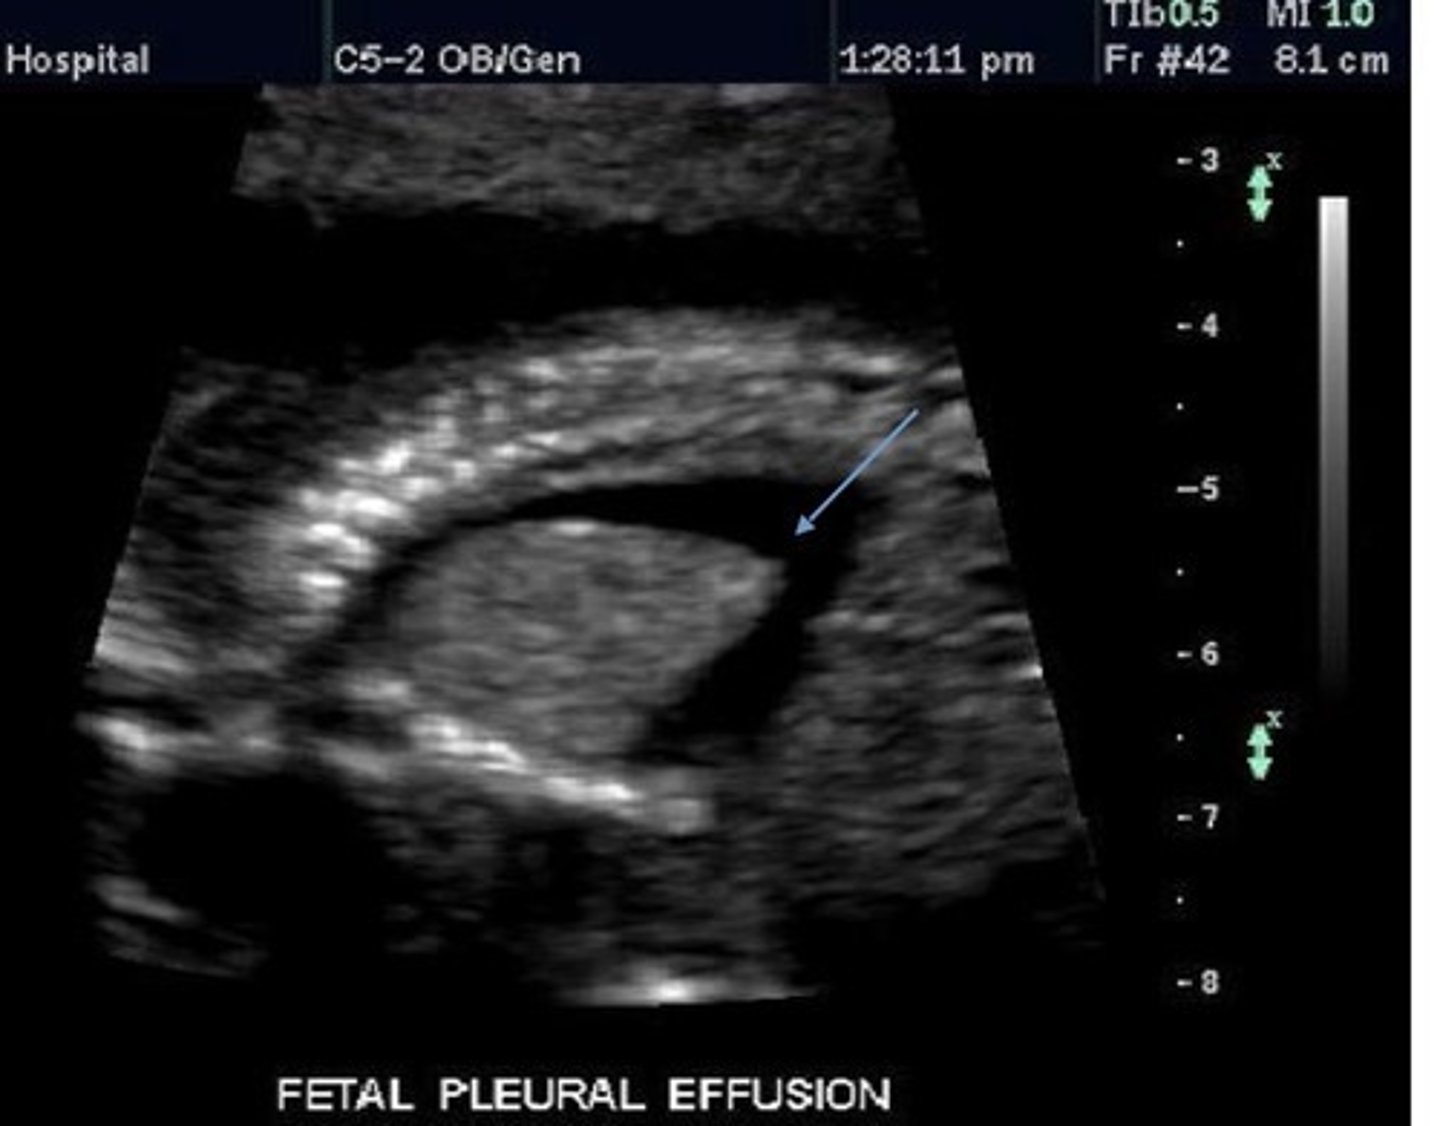

Pleural Effusion

Fluid in pleural cavity